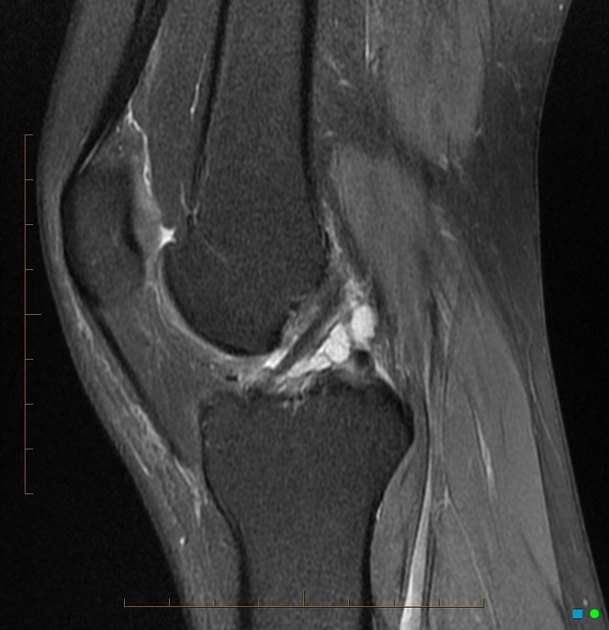

Nang sụn chêm (Meniscal cyst)